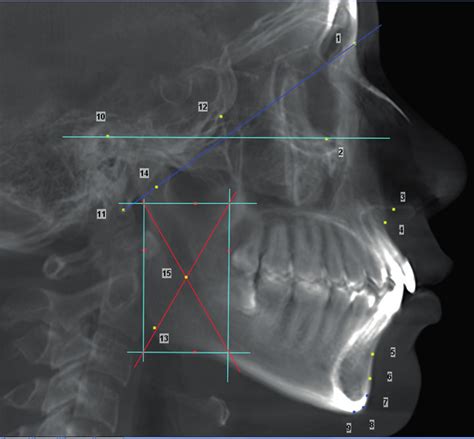

Los signos más visibles del desgaste dental incluyen dientes aplanados o con bordes irregulares, fisuras en el esmalte, aumento notable de la sensibilidad dental y, en casos severos, incluso fracturas dentales. Los síntomas comunes del bruxismo incluyen dolor de cabeza, dolor de mandíbula, dolor en los dientes y dolor de cuello. Otro de los problemas del bruxismo es que puede afectar a las articulaciones temporomandibulares (ATM), formada por los huesos y músculos, ligamentos y cápsula articular que permiten abrir y cerrar la boca.

Un bruxismo severo también podría comportar un trastorno de la articulación Temporo Mandibular (ATM).

El tratamiento del bruxismo tiene la finalidad de limitar el daño en los dientes, pero especialmente en la articulación temporo-mandibular (ATM), algunos de los tratamientos pueden incluir diferentes modalidades, como las técnicas conductuales, los tratamientos conservadores, las infiltraciones intraarticulares o artrocentesis, la artroscopia, la cirugía abierta o la colocación de una prótesis de ATM.